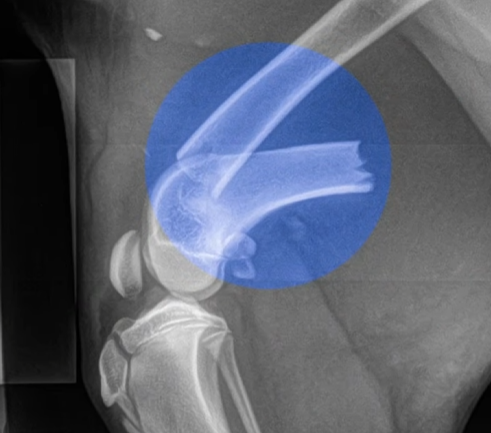

Qua thăm khám lâm sàng và hình ảnh X-quang, đội ngũ bác sĩ xác định bé bị gãy thân xương đùi (Femoral Shaft Fracture). Đây là một chấn thương nặng, đòi hỏi phải can thiệp ngoại khoa kịp thời để tránh nguy cơ tật nguyền vĩnh viễn. Sau khi được bác sĩ đánh giá và cân nhắc các phương án, chủ của Dola đã thống nhất thực hiện phẫu thuật bằng nẹp PRCL để đảm bảo khả năng phục hồi tốt nhất khi chó bị gãy xương đùi.